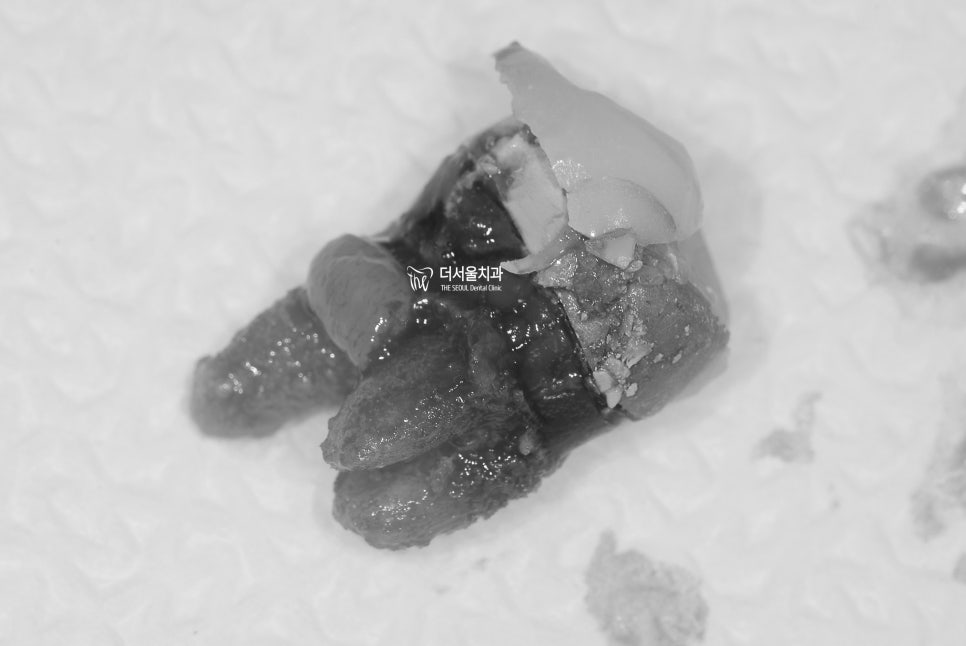

어금니 발치

역시나, margin 쪽으로 우식증들이

넓게 퍼져있는 것을 볼 수 있었고

뿌리 쪽을 보면 염증조직이 있었기에

granulation tissue 들도 딸려나온 것을

함께 볼 수 있습니다.